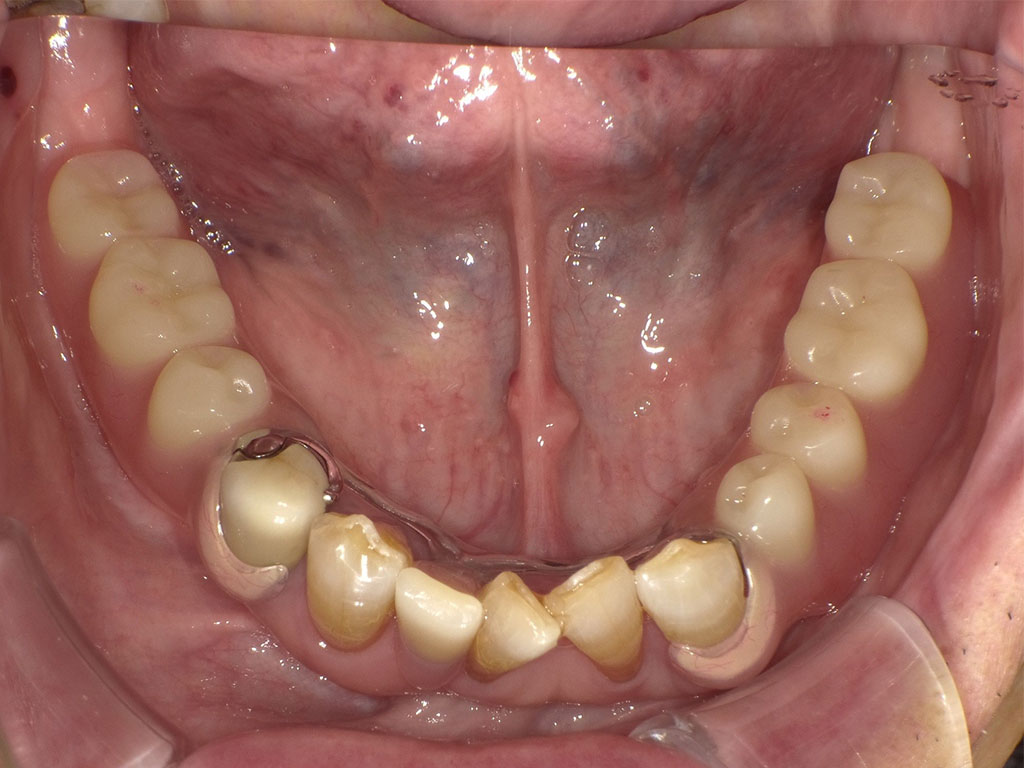

【入れ歯(義歯)症例2】80代男性

80代男性・横浜市在住。元々入れ歯をしていたが、支えていた歯が折れてしまったため、下顎にクラスプの目立たない自費の入れ歯を作成。異物感が少ないことと、目立ちにくいことを両立させて欲しいという要望でした。

Before1

患者の症状

80代男性。横浜市在住。今まで下顎に保険の入れ歯を装着していたが、入れ歯を支えていた歯が折れてしまった状態で来院。今まで使用していた保険の入れ歯を使用しているが不満で、インプラント手術も怖いということで自費の入れ歯をご希望とのこと。